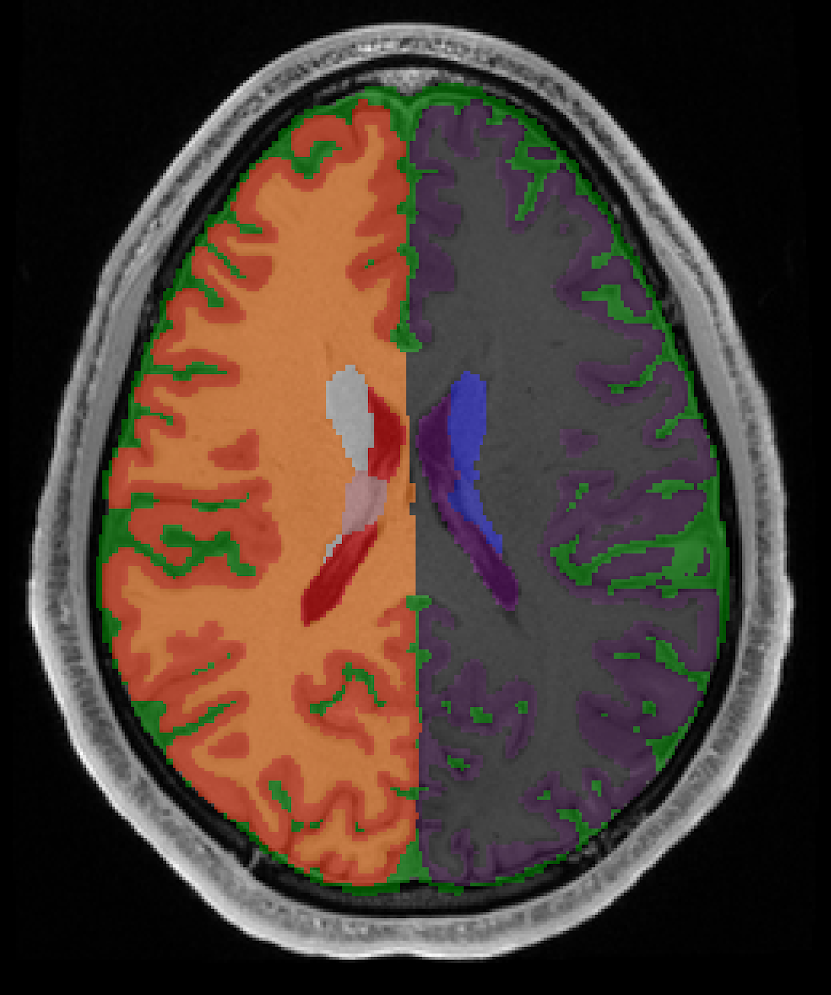

Neuroimage segmentation

There are various tasks of segmentation in nueroimaging, depending on what the region of interest is.

Some are separable by intensity, while some are very structure or relative location dependent.

There are various tasks of segmentation in neuroimaging, depending on what the region of interest is.

Multiple modalities, species and regions create different needs, hence different models and algorithms per task